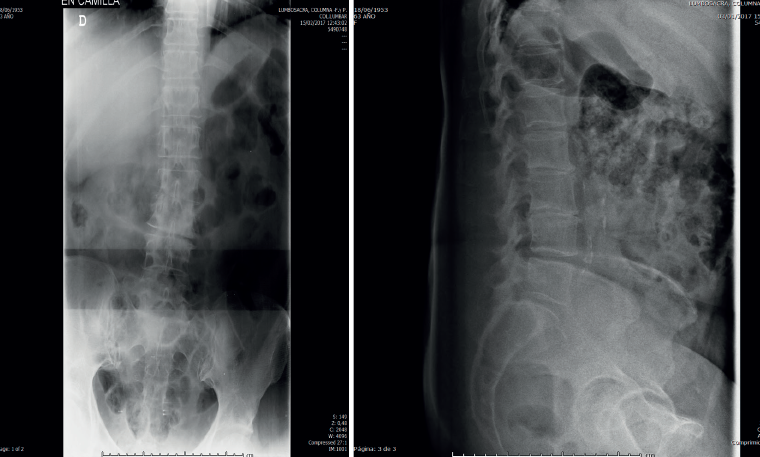

Figura 1. Radiografías de frente y de perfil lumbares.

• La radiología simple lumbar (Figura 1) de frente y de perfil muestra grave discopatía L2/L3 con práctica desaparición del disco intervertebral.